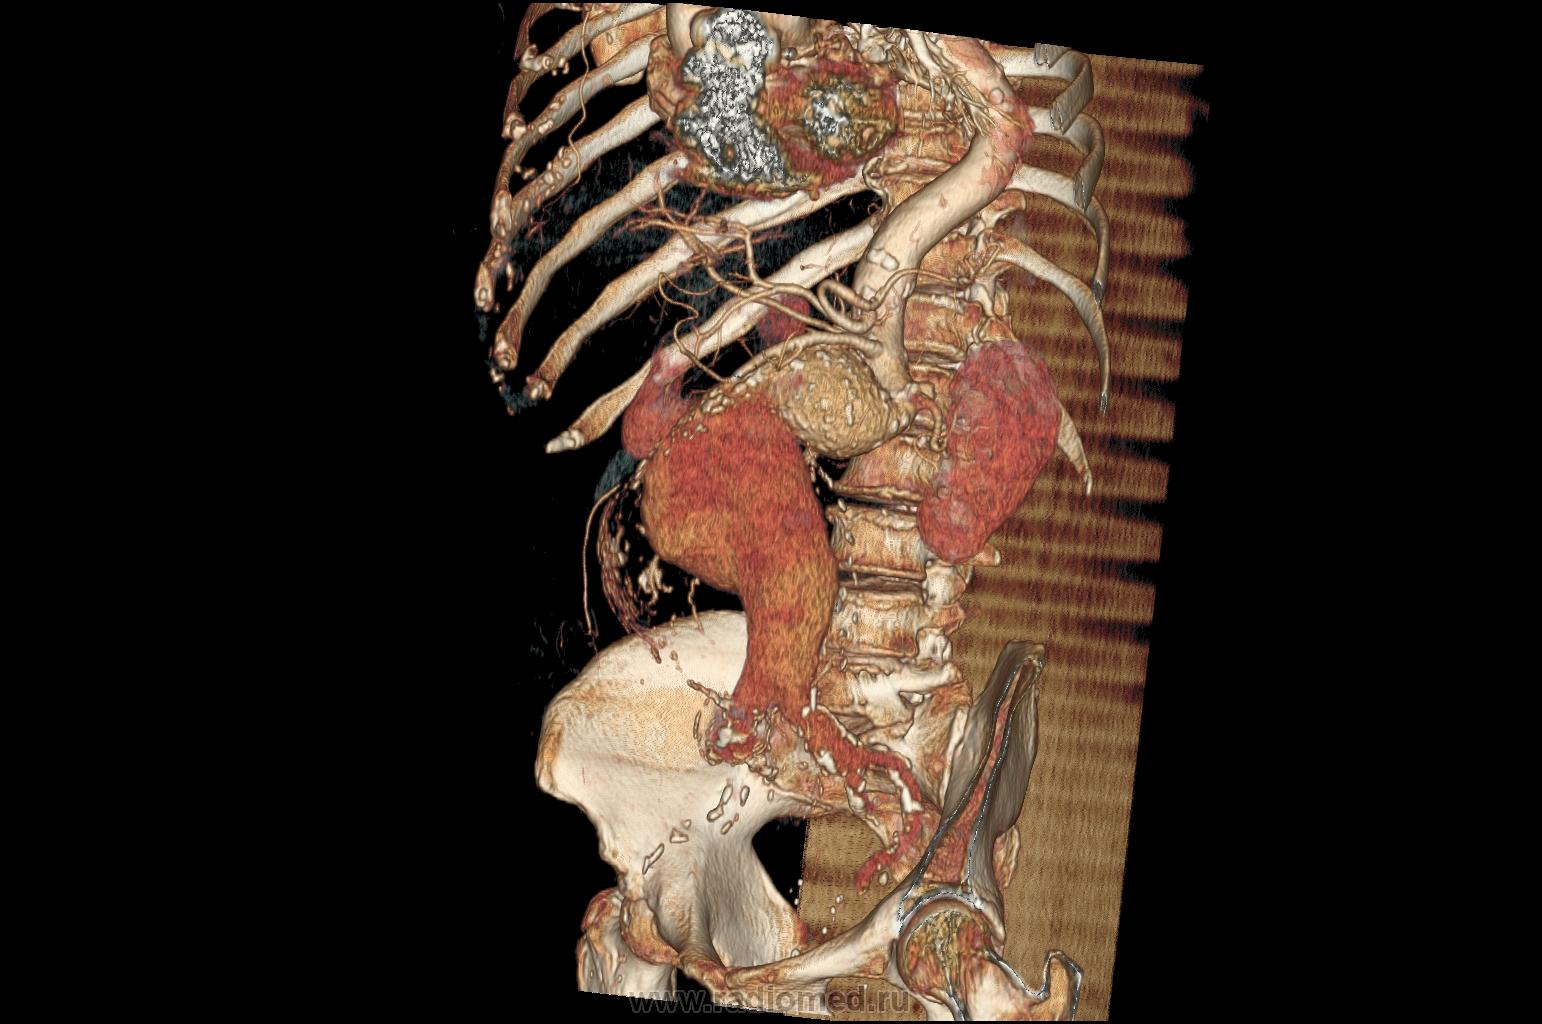

Наблюдение Tatarin

Женщина 77 лет. Жалобы на боли в животе. Пальпируется образование в околопупочной области живота. Аневризмы брюшной аорты и обеих общих подвздошных артерий.